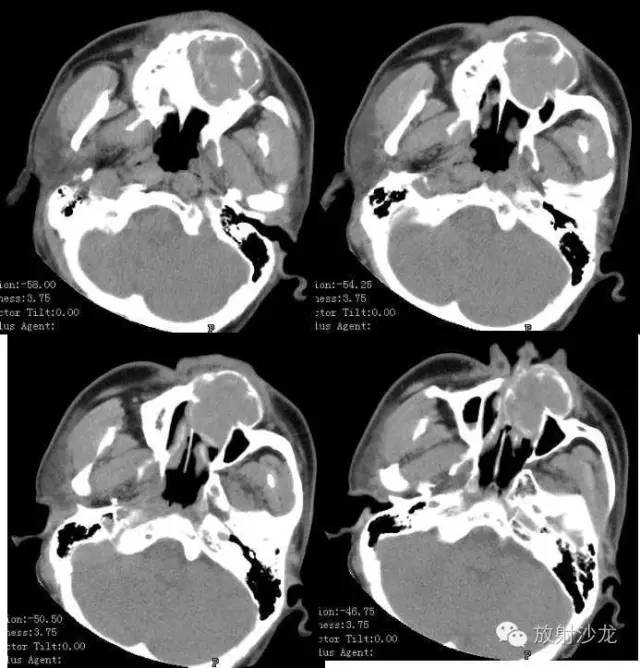

【术前CT扫描图像】

术前CT诊断:左侧下颌骨不规则膨胀性骨质破坏区,内可见软组织及残存骨嵴,病灶累及牙槽骨及筛窦壁,考虑造釉细胞瘤可能性大。